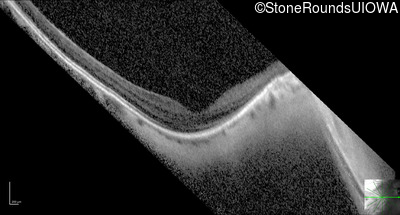

Optical Coherence Tomography - Right - 20/25 -3

Exemplar / OCT Stack

OCT Stack